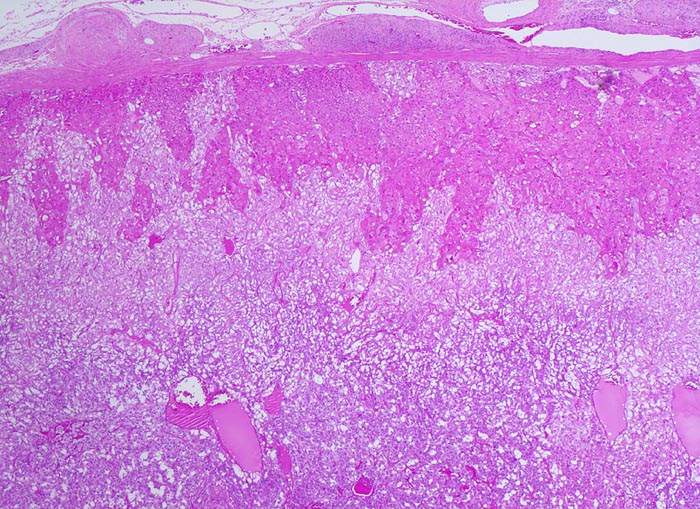

Phaeochromozytom

Nebenniere

Der gefässreiche basophile Tumor ist nicht bekapselt. Der Tumor infiltriert die Nebennierenrinde zungenförmig. Im periadrenalen Weichteilgewebe sind Anschnitte eines peripheren Nerven erkennbar.

Der Patient klagt über rezidivierende Kopfschmerzen seit zirka zwei Monaten. In letzter Zeit hat er Alcacyl genommen, jedoch ohne Erfolg. Die Computertomographie des Abdomens zeigt einen 5cm grossen Tumor im Bereich der rechten Nebenniere. Die Familienanamnese für multiple endokrine Neoplasien (MEN) ist bland.

25